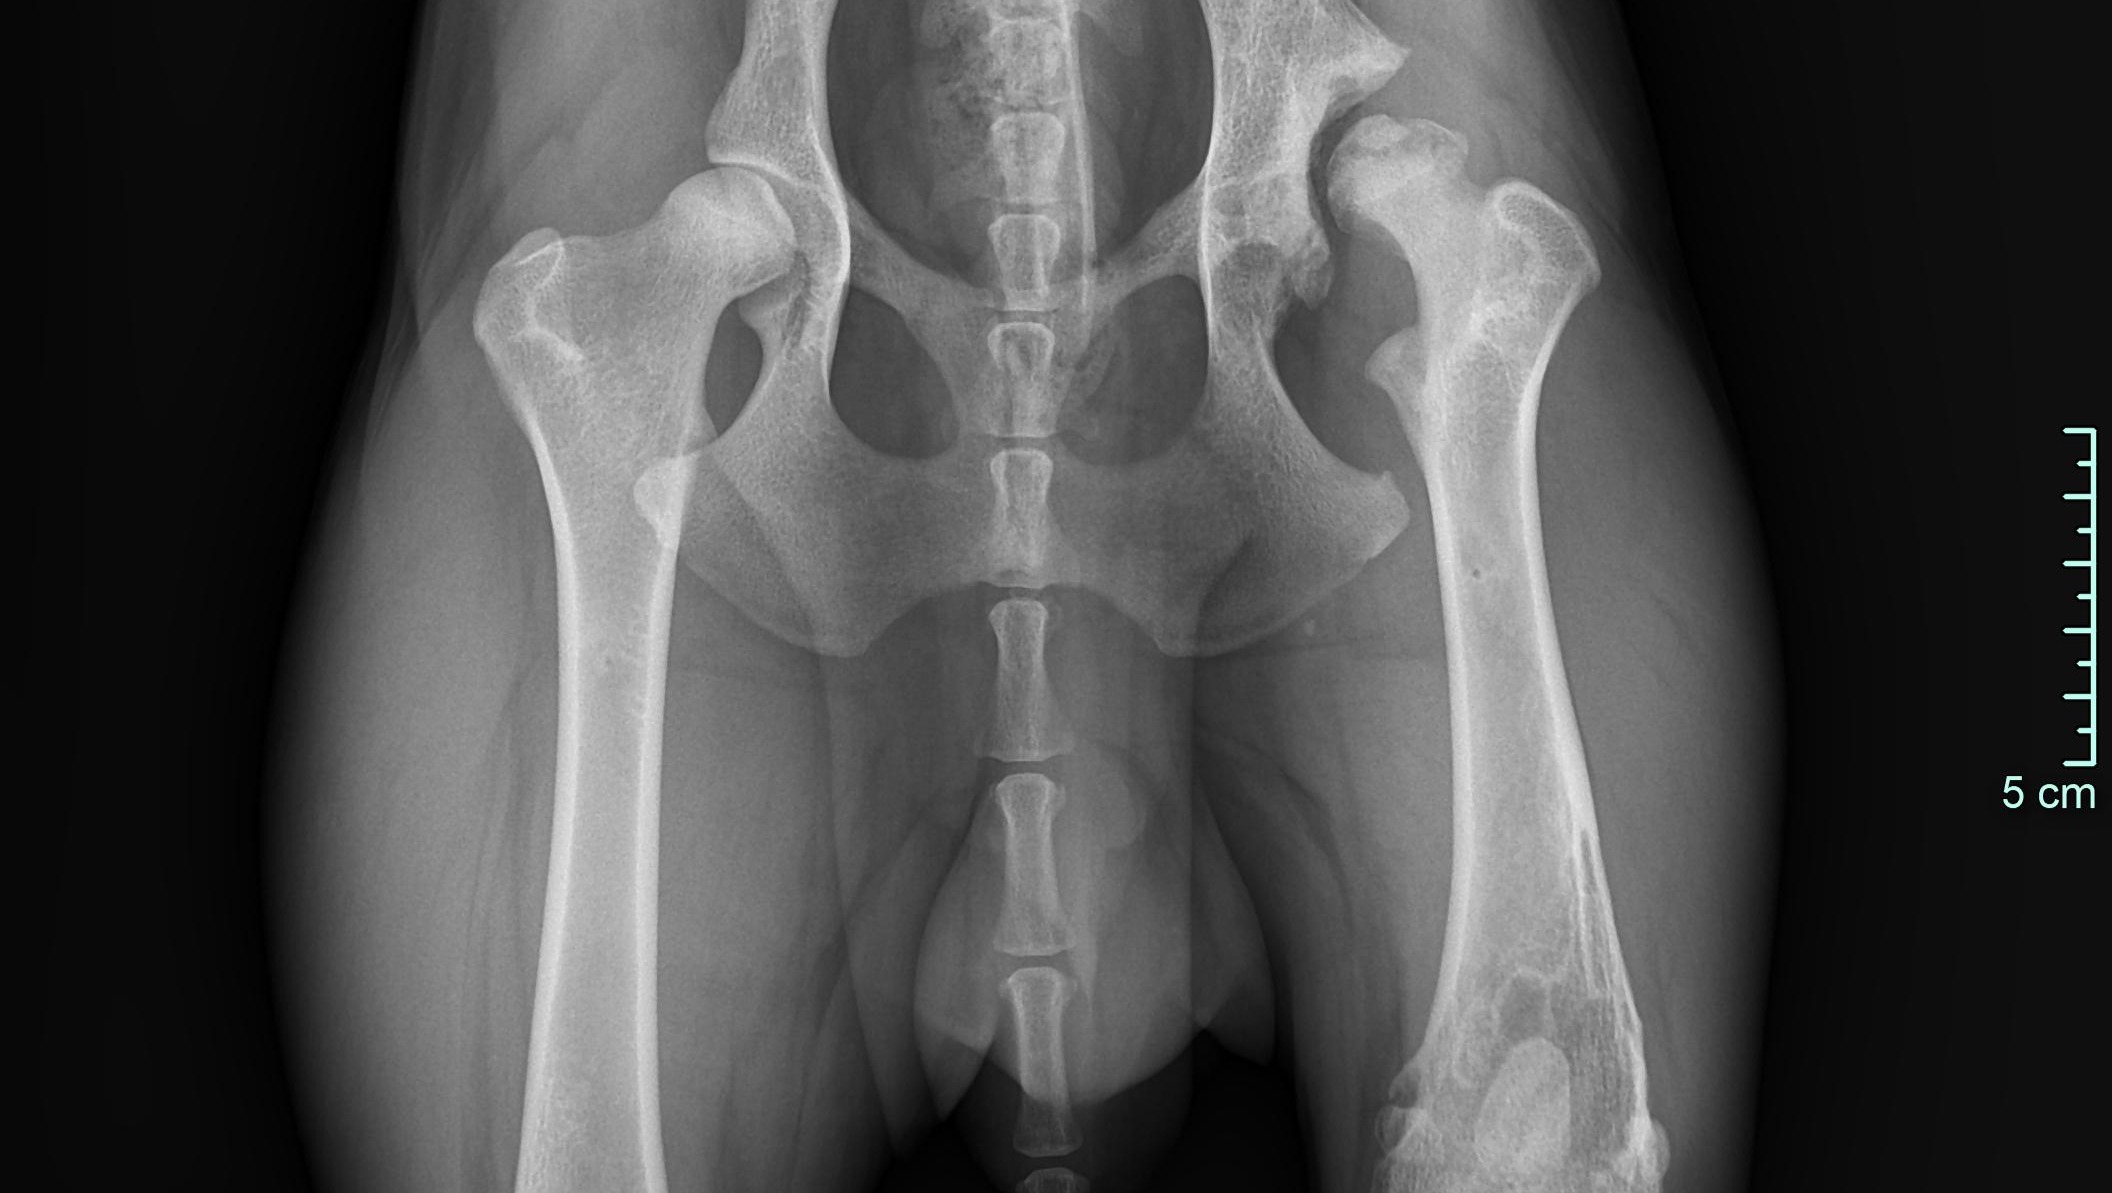

Röntgenaufnahmen und CT-Scans haben zig alte Frakturen und beginnende Arthrosen in seinem jungen Körper aufgedeckt. Ein gerade einmal einjähriger Hund, der bereits mit so vielen physischen Belastungen zu kämpfen hat. Doch die Medizin hat uns nicht im Stich gelassen: Aus seinem Ellbogen wurden Knochenfragmente entfernt, und er bekam ein künstliches Hüftgelenk – ein kleines Wunder der modernen Tiermedizin! Diese Eingriffe bieten ihm die Chance auf ein halbwegs normales Leben.

X-rays and CT scans have revealed countless old fractures and incipient arthrosis in his young body. A dog who is only one year old and already has to deal with so many physical stresses. But medicine has not let us down: bone fragments were removed from his elbow and he received an artificial hip joint - a small miracle of modern veterinary medicine! These operations offer him the chance of a somewhat normal life.